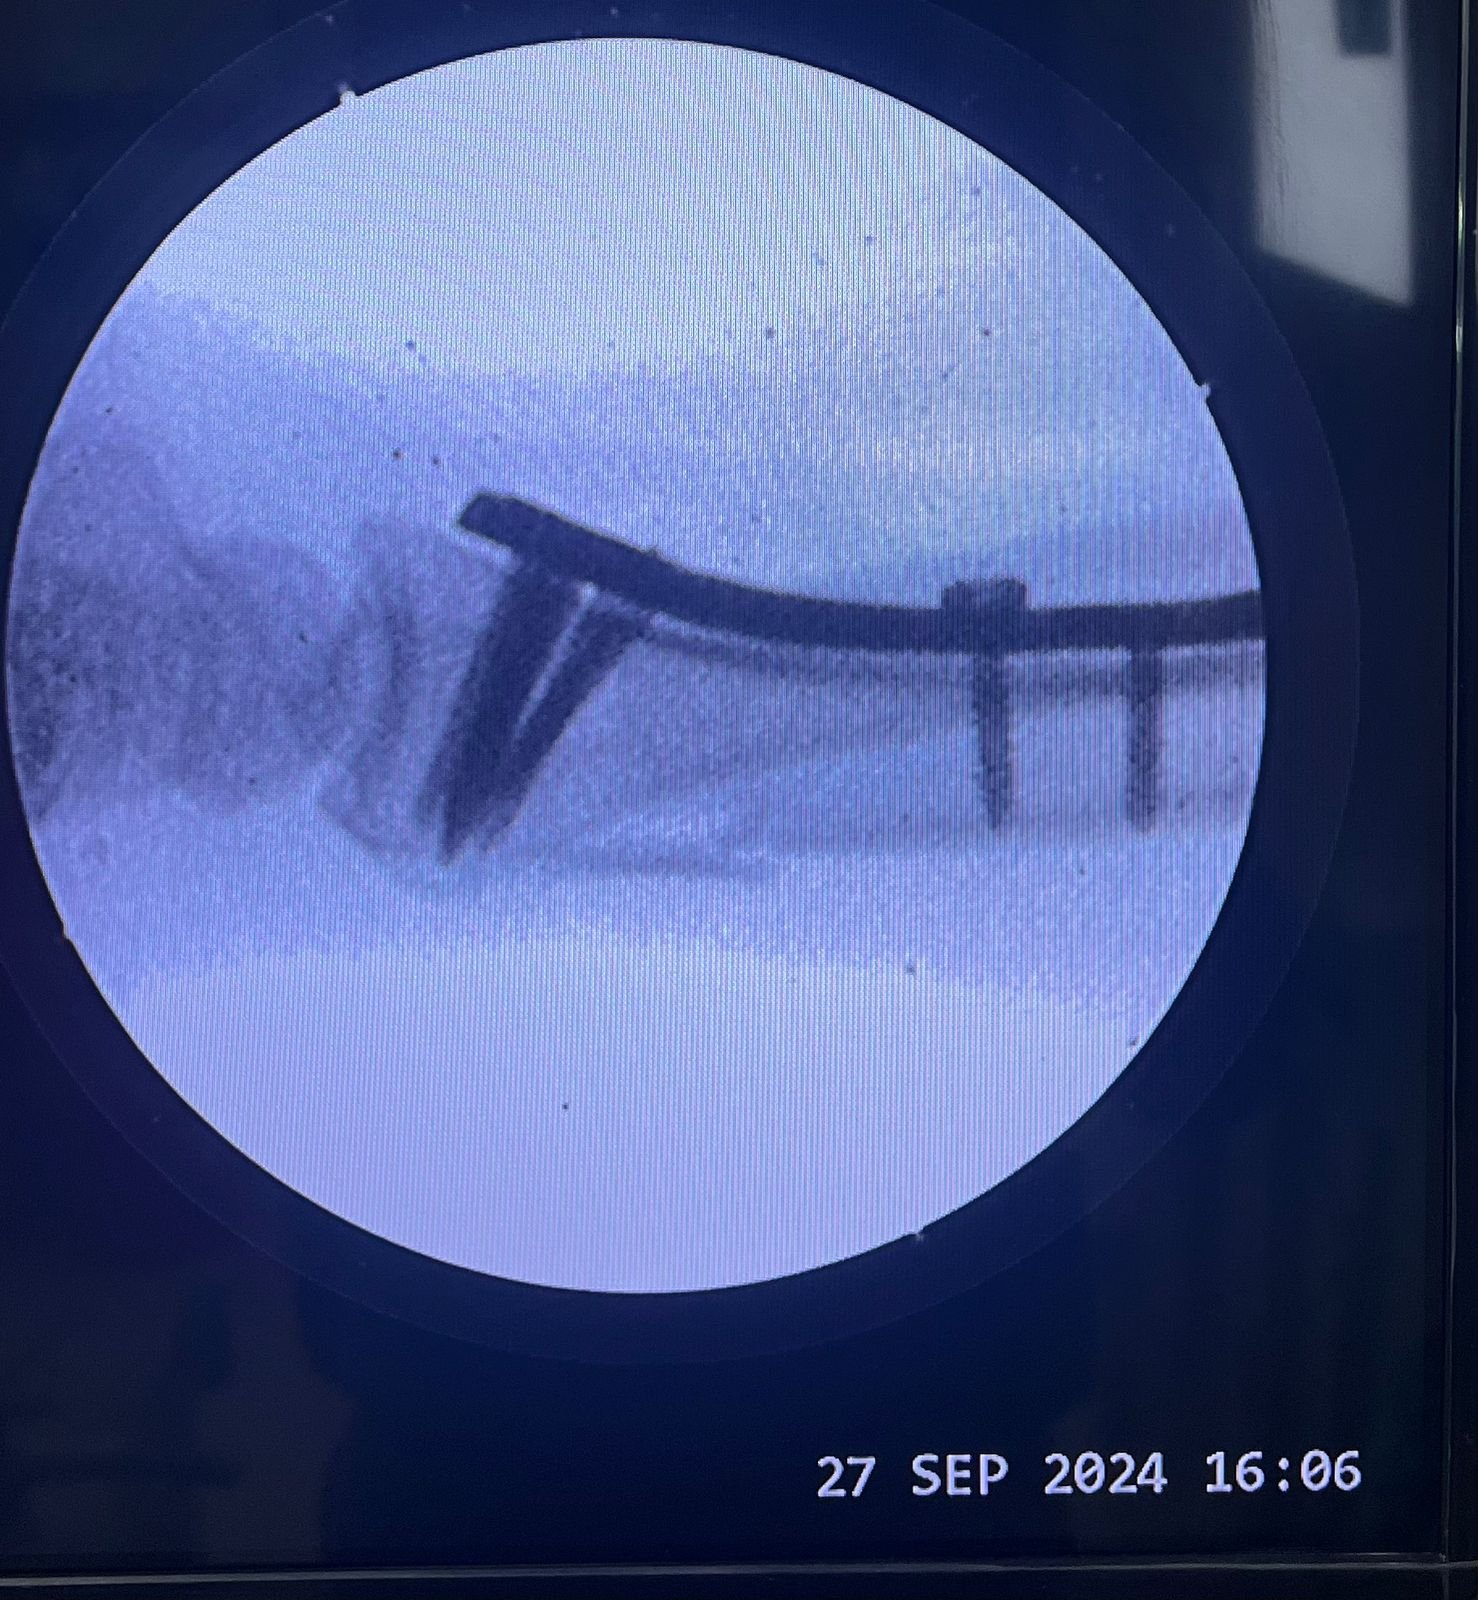

Heal fracture pre & postop | Clavicle fracture pre &

postop | Congenital foot deformity pre & post